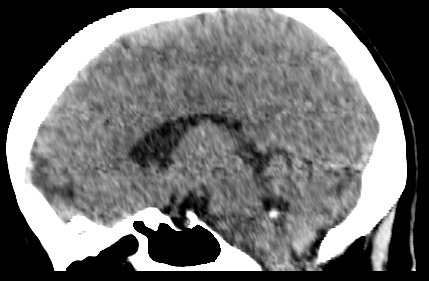

女,46岁,头晕1周。(第四脑室点状高密度灶,ct值约为65hu)。

四脑室脉络从钙化。

第四脑室脉络丛钙化。